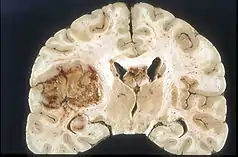

Building upon the study by Umemura et al. and ATX-70, it was found that 24h after administration of the sonosensitizer had improved efficacy when ultrasound was applied compared to immediate administration.[21][1] It was also determined that most ultrasound frequencies range between 1-3 MHz and 0.5-4W/cm^2. Higher frequencies at values such as 20W/cm^2 and 25W/cm^2 resulted in large necrotic lesions.[73][1] This established a relationship between sonosensitizer formulation and ultrasound intensity to necrosis. Other studies have continued to innovate upon this by controlling drug ultrasound interval (DUI) for different sonosensitizers in order to determine the optimal time period to apply the ultrasound for improved efficacy.[58][1] In addition, it has been shown that SDT can disturb surrounding vasculature in tumors.[1][58] This has been shown in studies by Gao et al. with 5-ALA in mice and human umbilical vein endothelial cell lines through inhibition of microvessel density and cell proliferation, migration, and invasion.[58][1]